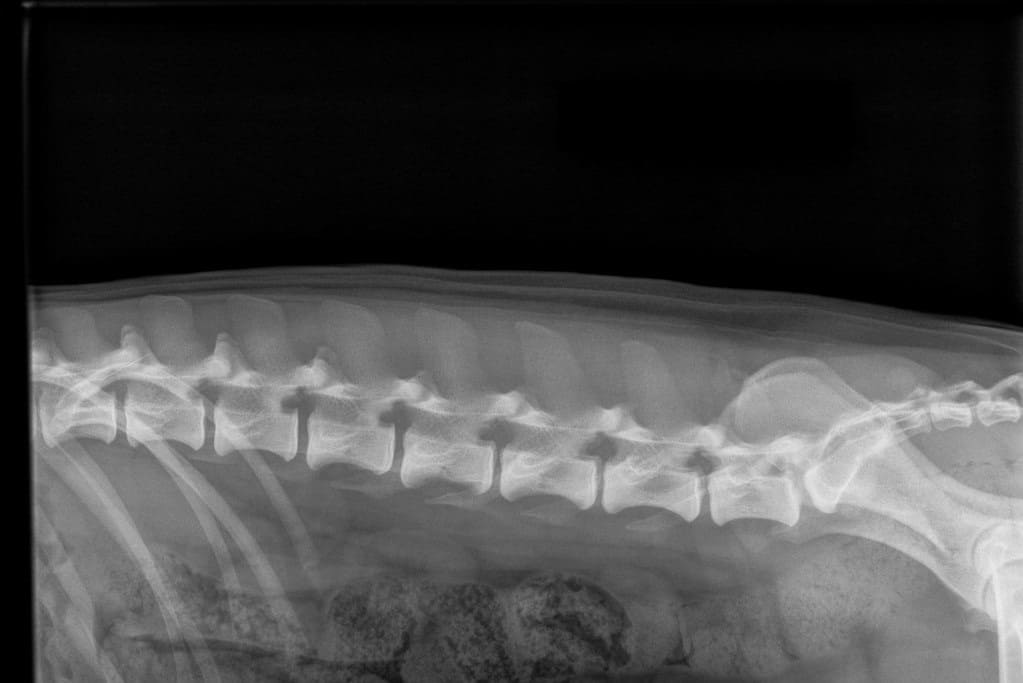

normal spine

A normal canine spine consists of 7 cervical (C1-7), 13 thoracic (T1-13), 7 lumbar (L1-7) and 3 sacral vertebras (S1-3) resulting the total of 30 vertebras. Calculation starts from first thoracic vertebra (T1). The number of caudal vertebras (CD) vary.

Sacrum connects the lumbar spine to pelvis. It’s a part of the pelvis and it lies between the lumbar spine and tail. Sacrum is strong, triangular in shape and it sits between the hip bones. Normal sacrum consists of three fused vertebral segments; S1, S2 and S3.